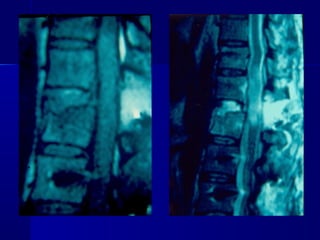

MMRRII

–UUsseeffuull ttoo eevvaalluuaattee

ddiissccrreeppaannccyy

bbeettwweeeenn cclliinniiccaall

eevvaalluuaattiioonn aanndd xx--

rraayy // CCTT ffiinnddiinnggss

–DDiisscc hheerrnniiaattiioonn

–LLiiggaammeennttoouuss

iinnjjuurryy